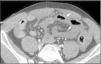

Varón de 31 años trasladado a urgencias de nuestro hospital por politraumatismo tras accidente de tráfico. Se realizó TC «total body» en donde se apreció hemoperitoneo, escaso neumoperitoneo y engrosamiento difuso de asas intestinales (fig. 1). Existía ausencia de realce tras contraste intravenoso (CIV) de un asa yeyunal, compatible con hipoperfusión (fig. 2) y focos de perforación intestinal (fig. 1). Se realizó cirugía urgente que confirmó el asa isquémica tras avulsión de vasos mesentéricos de pequeño calibre. La avulsión de los vasos mesentéricos por traumatismo abdominal cerrado es una entidad infrecuente, en especial sin lesión de víscera sólida asociada. Aunque el hematoma mesentérico o el extravasado de CIV son signos más específicos, debe sospecharse ante un segmento intestinal con pared engrosada e hipoperfundida, neumoperitoneo y hemoperitoneo sin lesión de víscera sólida.